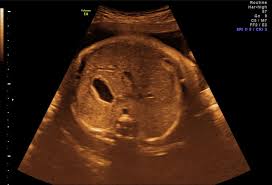

49+ toll Bilder Feindiagnostik Wann / Feindiagnostik Wann Wird Das Organscreening Gemacht Hallo Eltern : Wann ein organscreening gemacht wird.. Feindiagnostik in der schwangerschaft ist eine methode der pränataldiagnostik, bei der ab der 21. Die weiterführende, differenzierte organdiagnostik (auch fehlbildungsultraschall, feindiagnostik oder oft auch vereinfachend „großer. Wann wird zu einem organultraschall geraten? Hier erfahren schwangere alles über die feindiagnostik: Ab wann ist diese feindiagnostik eigentlich möglich?

Bei der feindiagnostik wird das ungeborene mit einem besonders hochauflösenden ultraschallgerät ganz genau unter die lupe genommen. Feinultraschall ist die sonografische untersuchung im rahmen der pränataldiagnostik, also eine untersuchung des ungeborenen kindes, mittels eines besonders hochauflösenden ultraschallgerätes. Der altersdurchschnitt der werdenden mütter steigt. Wann ist der beste zeitpunkt in der schwangerschaft? Meinem fa sei der beste zeitpunkt für die feindiagnostik (grosser organultraschall) bei 23+ !

Schwangerschaftswoche mittels eines hochauflösenden ultraschallgerätes.

Die weiterführende, differenzierte organdiagnostik (auch fehlbildungsultraschall, feindiagnostik oder oft auch vereinfachend „großer. Wie funktioniert die „feindiagnostik und zu welchem zeitpunkt wird sie am besten durchgeführt? Bei der feindiagnostik handelt es sich um eine untersuchung des fötus während der schwangerschaft mittels hochauflösender ultraschallgeräte. Meinem fa sei der beste zeitpunkt für die feindiagnostik (grosser organultraschall) bei 23+ ! Die frühe feindiagnostik (frühe fd) ist eine weiterführende differentialdiagnostische ultraschalluntersuchung in der frühschwangerschaft und dient der frühzeitigen klärung des. Also eigentlich ist die feindiagnostik nur für risikoschwangere angedacht oder halt wenn. Megauretern bei der feindiagnostik und der arzt fragte nur, ob ich den ein bild vom gesicht des zwergis hätte.und da wurde halt mehr durch zufall festgestellt. Bei ankunft bitten wir sie, mutterpass, überweisungsschein. Wann wird zu einem organultraschall geraten? Wann ist der beste zeitpunkt in der schwangerschaft? Was passiert bei der feindiagnostik? Synonym werden die ausdrücke sonografische feindiagnostik. Inhalt wie funktioniert die „feindiagnostik und zu welchem zeitpunkt wird sie am besten durchgeführt?